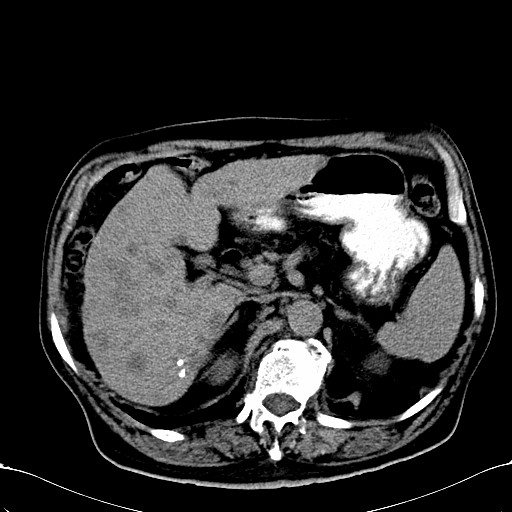

标题: CT28270:胰管扩张,肝多发占位 [打印本页]

标题: CT28270:胰管扩张,肝多发占位

患者,男,75岁。

考虑胰腺钩突癌并肝内转移,建议强化明确。

1)考虑胰头癌并肝脏多发性转移;建议行ct增强扫描检查。2)胃窦癌?建议行胃镜检查。

肝脏多方低密度结节,边缘模糊,考虑多发转移,胰管明显扩张,建议增强扫描钩突情况

肝脏多发低密度灶,胰头似呈低密度,胰管扩张,建议增强,

胰管显著扩张,但胆总管未见扩张征象,不太符合胰头占位!考虑慢性胰腺炎.胃窦占位并肝内转移可能!mrcp胃镜增强一起上!